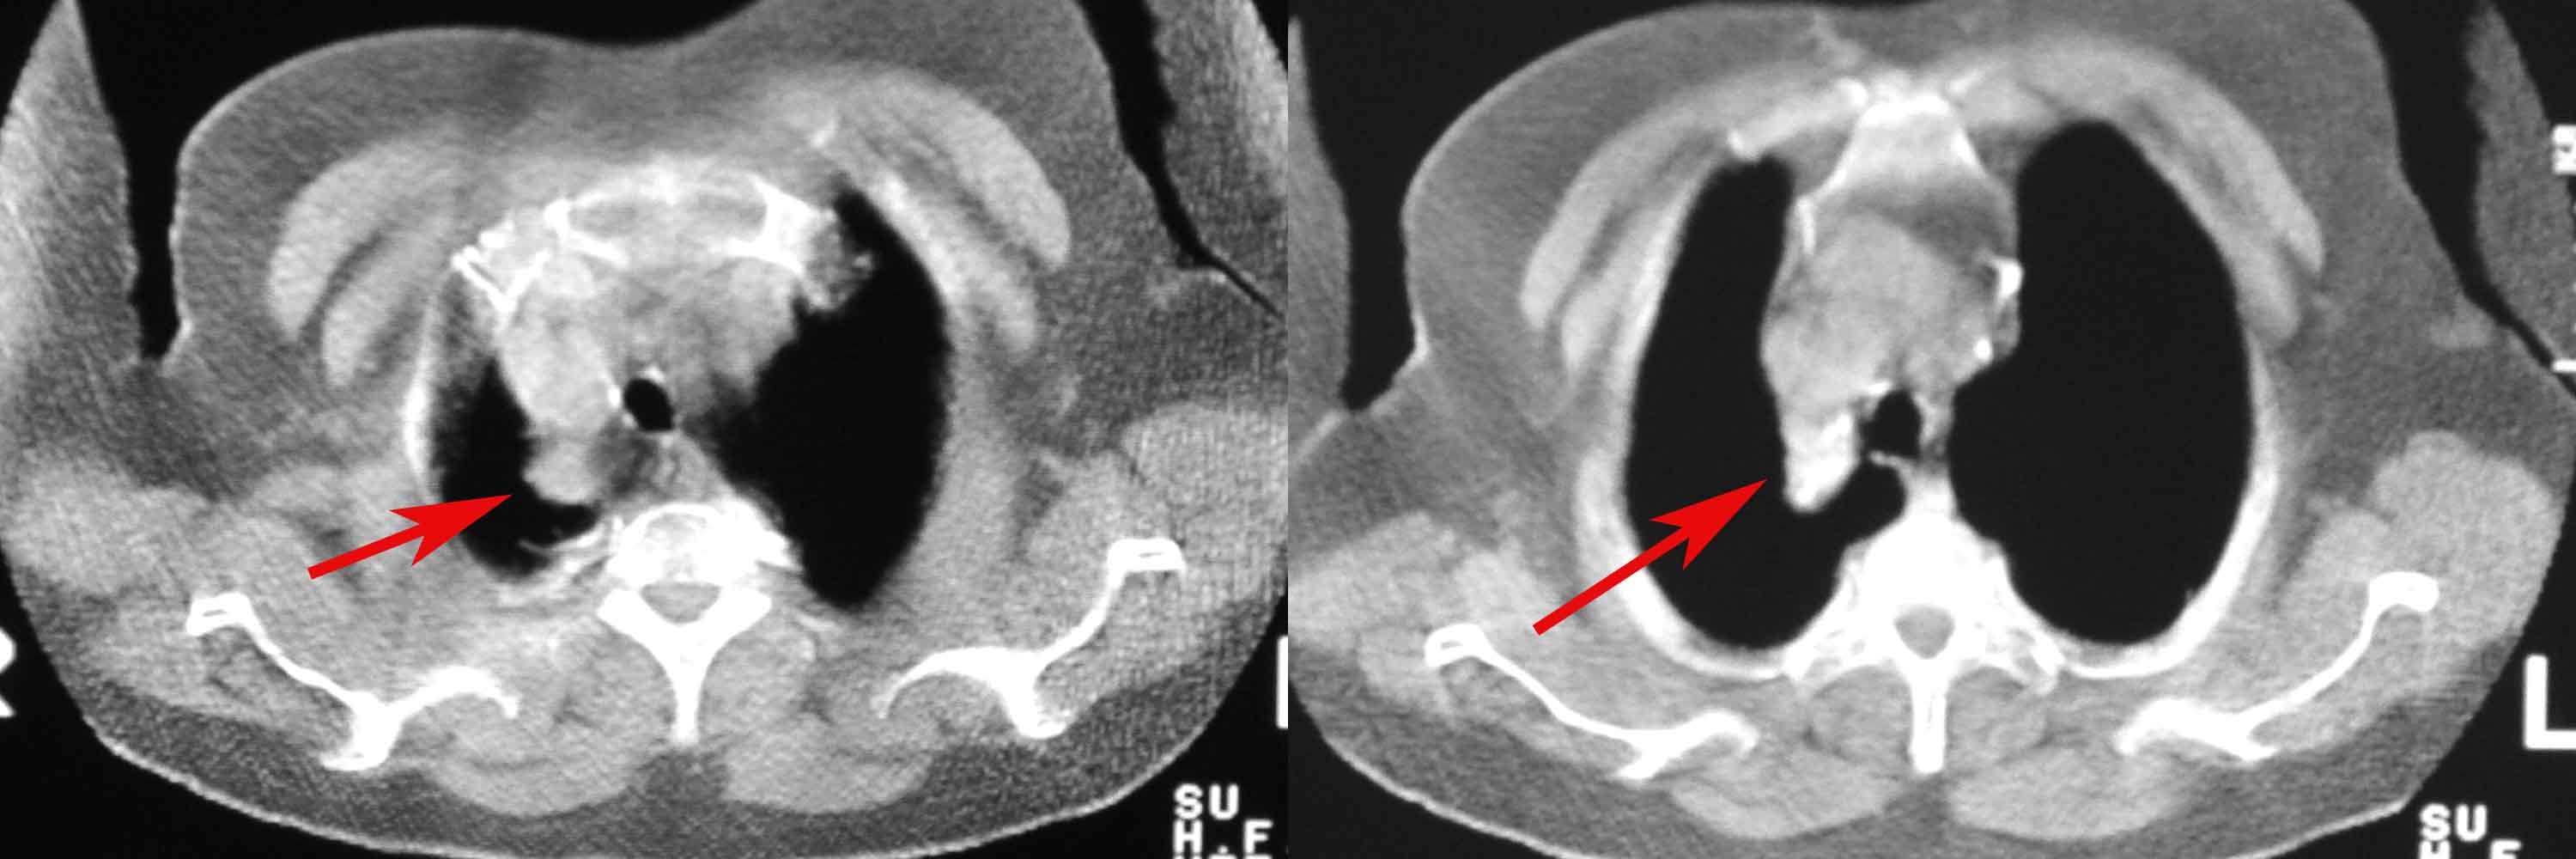

女78岁咳嗽咳痰无咳血平片报右上肺不张、慢支、肺气肿、请老师们帮忙看看,箭头所指是什么?是占位吗?有肺气肿吗?谢谢

箭头所指----多考虑-----右头臂静脉旁淋巴结钙化

可能是逾曲的头臂血管

可能是纡曲的头臂血管——支持。

箭头所指考虑血管影

箭头所指考虑血管影;纵隔内及双肺门区多发淋巴结钙化;不支持肺气肿。

箭头所指考虑血管影(头臂血管);纵隔内及双肺门区多发淋巴结钙化;不支持肺气肿。